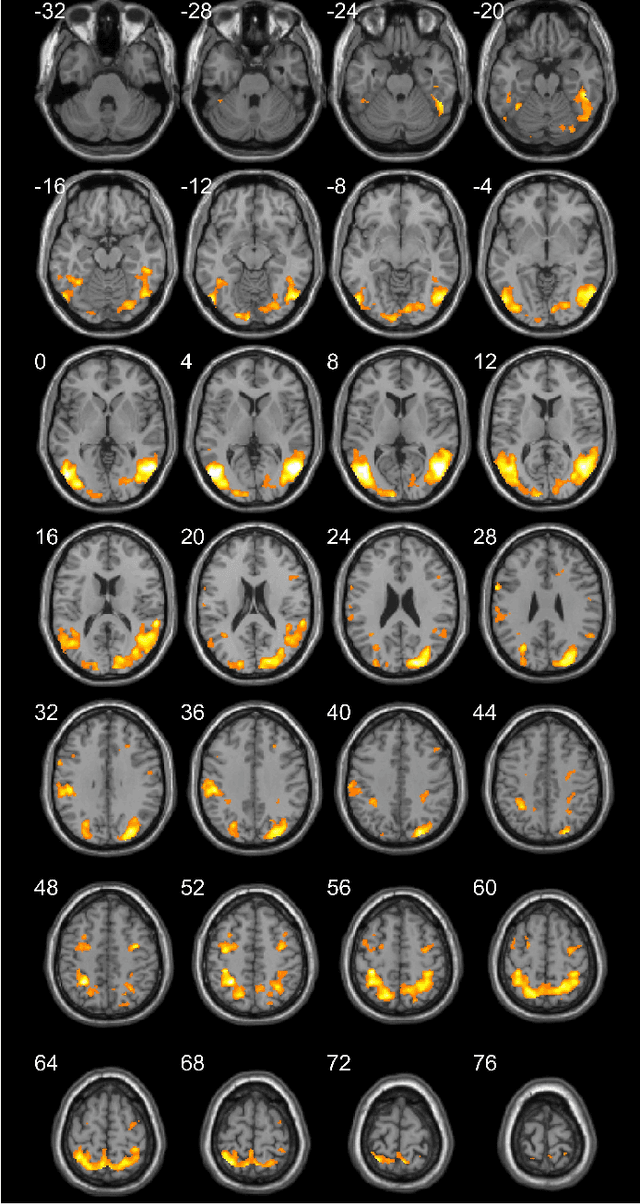

Abstract:Functional magnetic resonance imaging (fMRI) is one of the most popular methods for studying the human brain. Task-related fMRI data processing aims to determine which brain areas are activated when a specific task is performed and is usually based on the Blood Oxygen Level Dependent (BOLD) signal. The background BOLD signal also reflects systematic fluctuations in regional brain activity which are attributed to the existence of resting-state brain networks. We propose a new fMRI data generating model which takes into consideration the existence of common task-related and resting-state components. We first estimate the common task-related temporal component, via two successive stages of generalized canonical correlation analysis and, then, we estimate the common task-related spatial component, leading to a task-related activation map. The experimental tests of our method with synthetic data reveal that we are able to obtain very accurate temporal and spatial estimates even at very low Signal to Noise Ratio (SNR), which is usually the case in fMRI data processing. The tests with real-world fMRI data show significant advantages over standard procedures based on General Linear Models (GLMs).